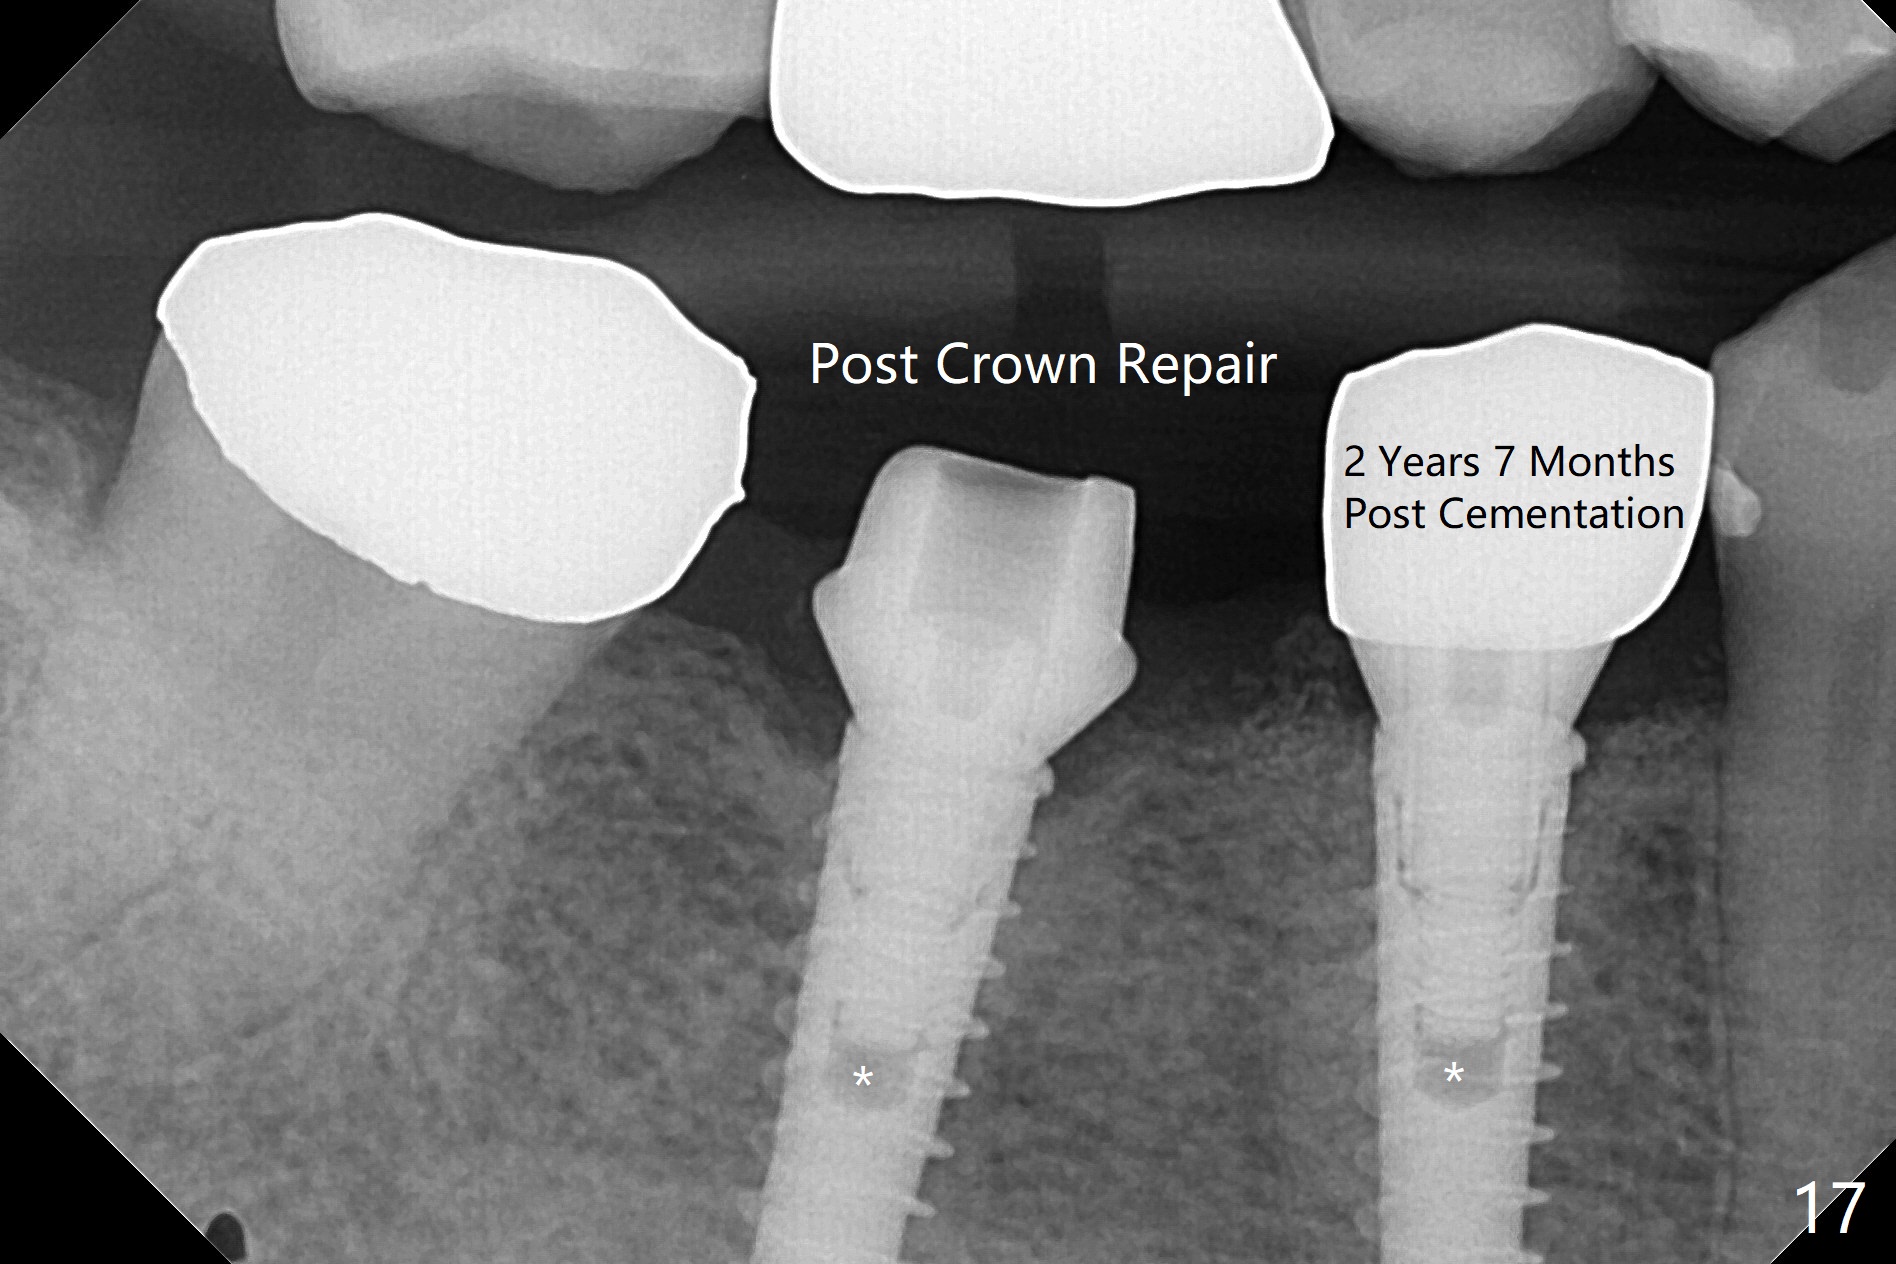

After incision, the ridge at #29 and 30 is found ~ 5 mm wide buccolingually. To place a 4x11 mm IBS implant at #30, the ridge is expanded using BEB technique (bone expansion and bending, Fig.1). It appears that the initial osteotomy at #29 is mesial (Fig.1 yellow dashed line: the distal surface of the root of the tooth #28). After moving the osteotomy distal, the final implant position at #29 (4x11 mm) is within normal limit (Fig.2). The bone at #29 seems to be not so dense that bending (using 1.6 mm drill) is not necessary (using Magic Split and Magic Expanders 3 and 3.8 mm). Later the implant at #30 (4x11 mm) is placed deeper (Fig.3). After placing bone graft around the implants/abutments and suturing, the ridge looks wider with apparent formation of the gingival bands around the abutments (Fig.4 *). Three months and a half postop, bone loss is minimal (Fig.5) and gingival bands forms around the abutments (Fig.6). Fig.7 is taken 1 month post cementation (panoramic X-ray). The patient chews normally 1 year (Fig.8) and nearly 2 years (Fig.9,10) post cementation. The crown at #31 needs recementation 2 years 7 months post #30 cementation; the incomplete seating of the abutment was noted for the first time (Fig.11). Five months later the patient is going to be retired and wants to travel abroad. After approval, the access hole was reopened; articulating paper shows under occlusion of the crown (Fig.12). Since the gap between the abutment and the implant is large, the abutment/crown complex seems to be necessary to be turned (Fig.13 curved arrow). The proximal surfaces of the crown need to be trimmed (straight lines). After turning, the crown sits down with screw tightening; the patient feels pain from the gingival cuff (Fig.14). After turning, the abutment appears to be completely seated (Fig.15). In fact the mesial and distal surfaces of the crown should have clearance from the neighboring teeth (Fig.14) so that pick-up impression is able to hold the crown/abutment complex securely (Fig.16: *). The crown is separated from the abutment after crown repair. They are seated together (loose connection) using the crown as a guide to seat the abutment. BW is taken without the crown. It appears that the abutment remains seated completely (Fig.17). The apical space is equal between #29 and 30 (Fig.17, as compared to Fig.5).